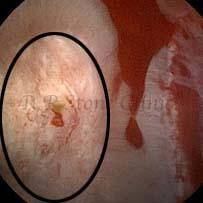

The Below Images Show Small Stones attached to the Renal Papillae.

These images are taken as snap shots from the video recording of RIRS Surgery done at our hospital. These are Randall’s Plaques seen with Digital FLEX XC & Digital FLEX XC S. The cream or whitish patches are seen on the tips of RENAL PAPILLAE as seen in images below.